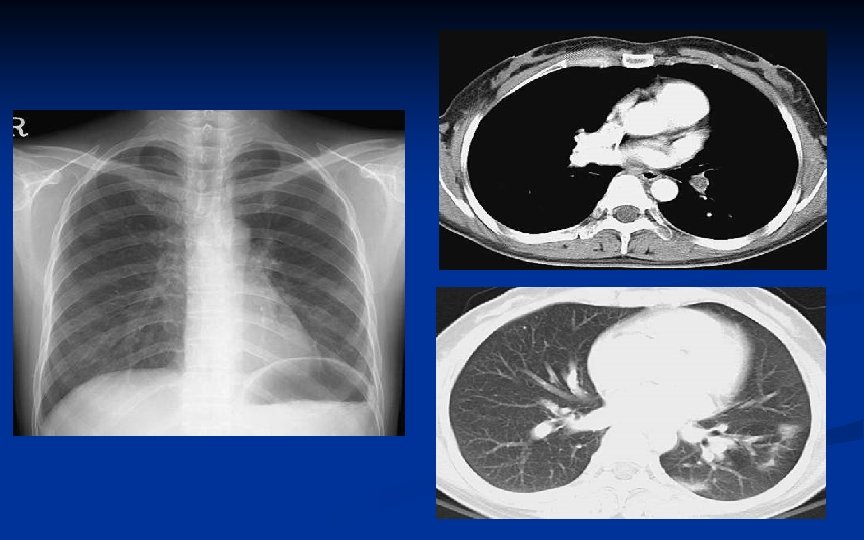

OSTEOSSARCOMA RX é a ferramenta mais valiosa para o diagnóstico correto Mais comum: lesão agressiva na metáfise de osso longo 10% são primariamente diafisários e 1% epifisários

OSTEOSSARCOMA Áreas blásticas e líticas Lesão permeativa com bordas mal definidas Na ruptura da cortical, massa de tecidos moles pode estar presente Triângulo de Codman (elevação do periósteo no limite do crescimento do tumor) Aparência de raios de sol e “final do cabelo”

OSTEOSSARCOMA RNM: ideal para avaliar extensão do tumor no osso e partes moles Cintilografia para procurar por metástases esqueléticas RX e CT pulmonar para procurar metástases (sítio mais comum) Realizar exames antes da biópsia

OSTEOSSARCOMA • Metástases pulmonares ocorrem precocemente – freqüentemente o fazem dentro de 2 anos após o diagnóstico